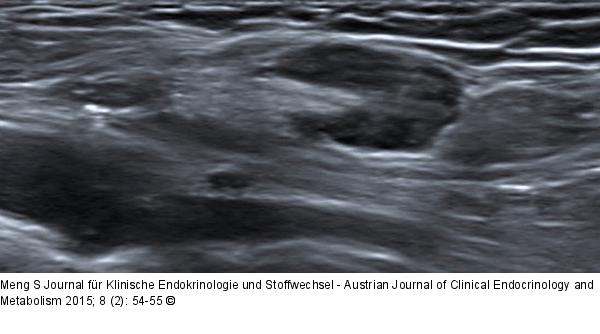

Abbildung 4: Ultraschall-Lymphknoten Fehlende Gleichmäßigkeit des Lymphknotenkortex. Besonders am rechten Rand des Lymphknotens fällt die exzentrische Verbreiterung des Kortex auf. Hodgkin-Lymphom-Rezidiv. |

Fehlende Gleichmäßigkeit des Lymphknotenkortex. Besonders am rechten Rand des Lymphknotens fällt die exzentrische Verbreiterung des Kortex auf. Hodgkin-Lymphom-Rezidiv. |